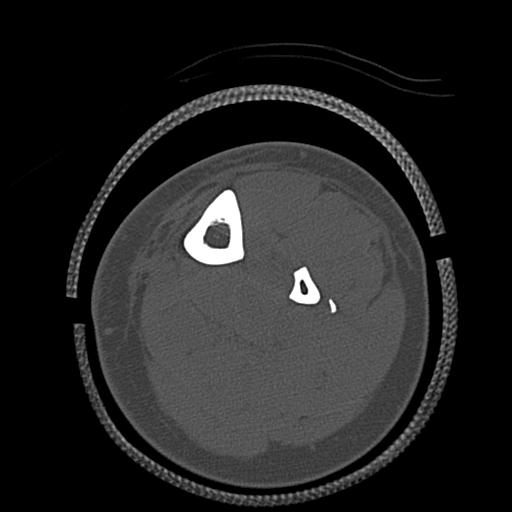

49554 3/13 膝 4R 3/16 4R 1/18 2R 78歳男性 膝蓋骨骨折